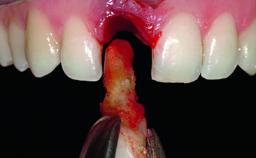

Replacement of an Upper Right Central Incisor with Root Resorption: Ridge Preservation, Early Placement of an RC Bone Level Implant

A 49-year-old female patient was referred for implant therapy to replace the upper right central incisor (tooth 11). The tooth had been assessed by an endodontist who diagnosed a vertical fracture of the root. The tooth had a hopeless prognosis and needed to be extracted. The patient was healthy and was not taking any medications. She was allergic to penicillin. The patient had high esthetic demands but her expectations were realistic. The extraoral examination revealed no facial asymmetries. The right temporomandibular joint demonstrated an opening click but was otherwise asymptomatic. The lip line was high with a significant gingival display.

Bone Augmentation Simultaneous|Vertical

Augmentation Materials Autogenous chips|Xenogenous|Membrane